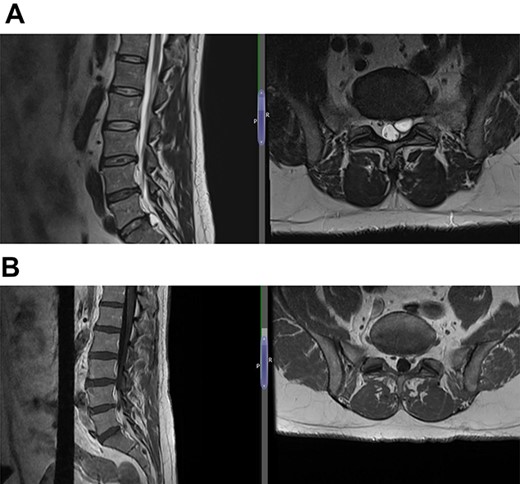

(A) Case 3—an early MRI demonstrates at L5/S1 level moderate diffuse disc bulge is seen with early bilateral facet joint degenerative changes; there is irritation of the L5 nerve roots bilaterally, and at L5/S1 level moderate left posterolateral disc bulge is seen irritating the S1 nerve roots bilaterally left more than right, and bilateral facet joint degenerative changes also noted at this level, and (B) case 3—a later MRI, the cystic changes noted at the L4-L5 level which clearly shows a connection with the intervertebral disc.

(A) Case 4—an initial MRI showing multilevel degenerative disc disease and a cyst at the lumbar L5/S1 which is causing impingement on the left S1 nerve root, and (B) case 4—comparison was made with the previous MRI; post-contrast scan shows that the L5-S1 left-sided cystic features have nearly diminished; no neoplastic lesion is detectable.